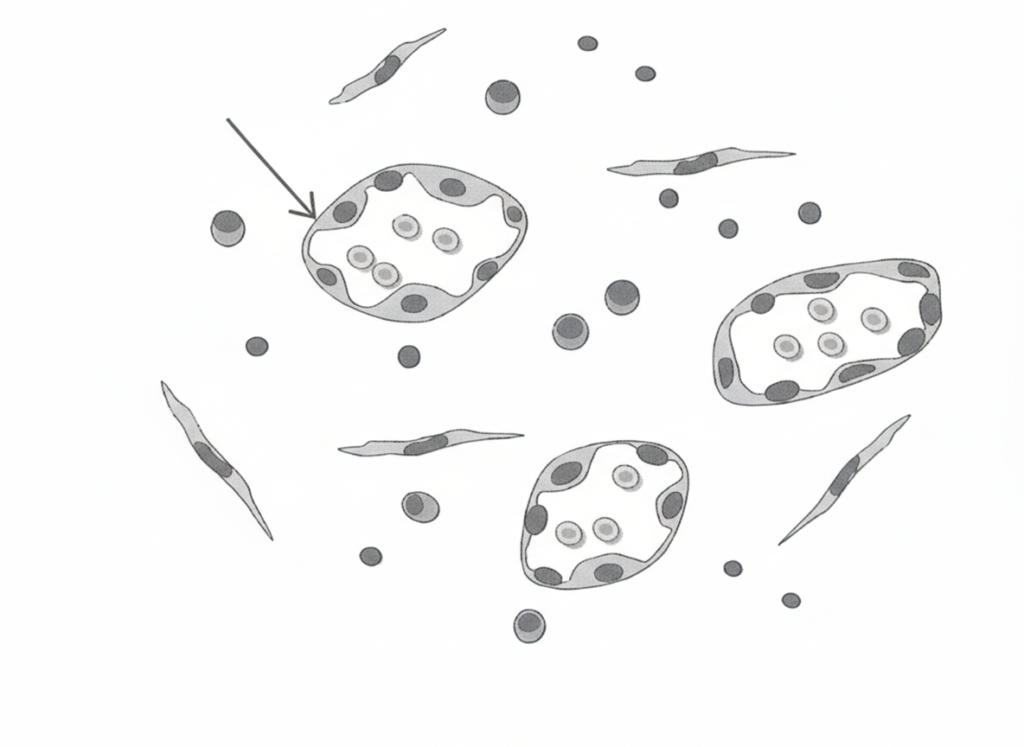

午前-10

肉芽組織を模式図に示す。矢印で示すのはどれか。1つ選べ。

a. 形質細胞

b. 毛細血管

c. リンパ球

d. 線維性結合組織

解答を見る

b